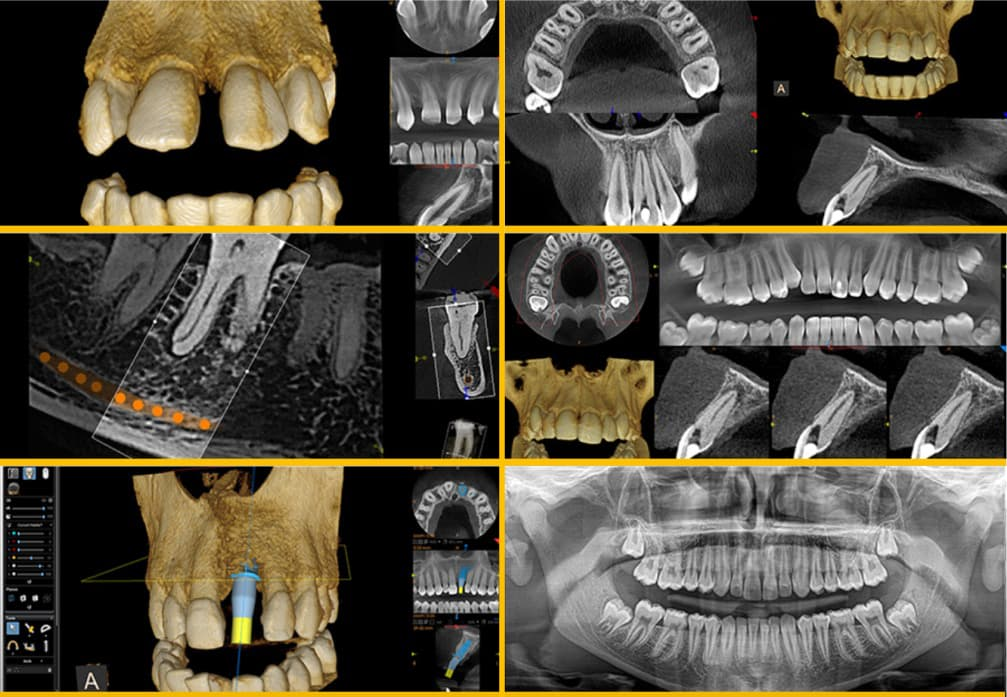

CT Scans

Did you know that you could get a CT scan in our very own dental practice? CT Scans are used in dental treatments to ensure accuracy for dental implants and give the highest chance of success due to a high level of detail and an ability to plot implant location.